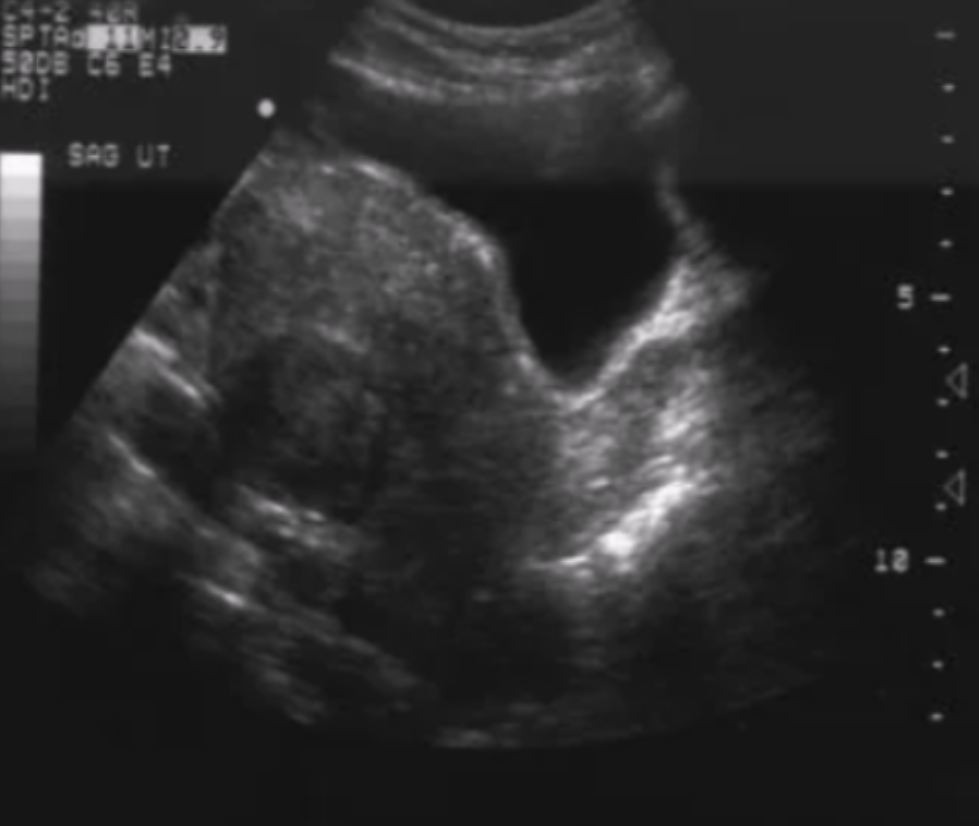

What type of fibroid is depicted in this image?

A. Intramural

B. Submucosal

C. Subserosal

D. Pedunculated

Subserosal